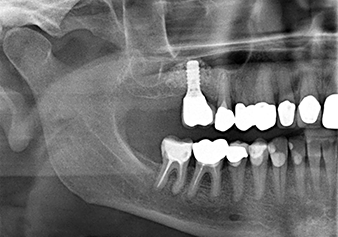

Implantation and prosthetic restoration

To move the augmentation material in the direction of the maxillary sinus atraumatically, the implant was inserted very slowly by hand (Fig. 9). In the process, the membrane was pushed in the cranial direction once again. After two months, the surgical site healed without irritation. Six months later, the x-ray check showed a significant increase in opacity as an indication of ossification (Fig. 10). The prosthetic restoration was carried out with a metal-ceramic crown.

The x-ray check shows a largely homogeneous peri-implant hard tissue structure

Fig.10: A good six months later, after the definitive crown had been incorporated, the x-ray check shows a largely homogeneous peri-implant hard tissue structure.